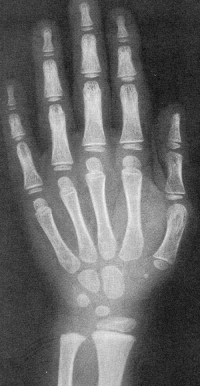

Sexo Masculino

1 ano

Sexo Feminino